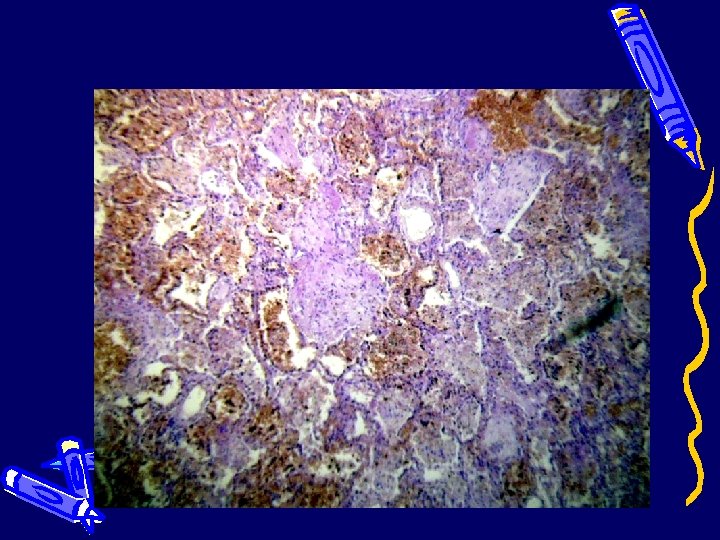

Селезенка (лимфоидное истощение, накопление клеток типа макрофагов)

Лимфатический узел (лимфоидное истощение, накопление клеток типа макрофагов в синусах)

Патологоанатомический диагноз: Основное заболевание (J 10. 0) Грипп А H 1 N 1 c пневмонией: геморрагический трахеобронхит, двухсторонняя полисегментарная серозно-геморрагическая пневмония, положительное вирусологическое исследование материала бронхов методом ПЦР ; отрицательное бактериологическое исследование легких ; пролиферация и накопление клеток типа макрофагов в синусах трахеобронхиальных и мезентериальных лимфатических узлов, красной пульпе селезенки, костном мозге, альвеолах; лимфоидное истощение селезенки, серозногеморрагический катаральный гастроэнтероколит.